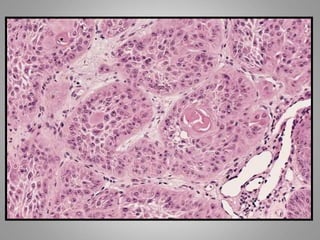

Malignant neoplasm of epithelial cells origin derived

from any of the three germ layer , are called

Carcinomas.

Cell of origin + Carcinoma

Squamous cells + carcinoma = squamous cell

carcinoma

Squamous cell carcinoma

Malignant neoplasm ofepithelial cells origin derived from any of the three germ layer , are called Carcinomas. Cell of origin + Carcinoma Squamous cells + carcinoma = squamous cell carcinoma Adenocarcinoma: One with a glandular growth pattern microscopically.